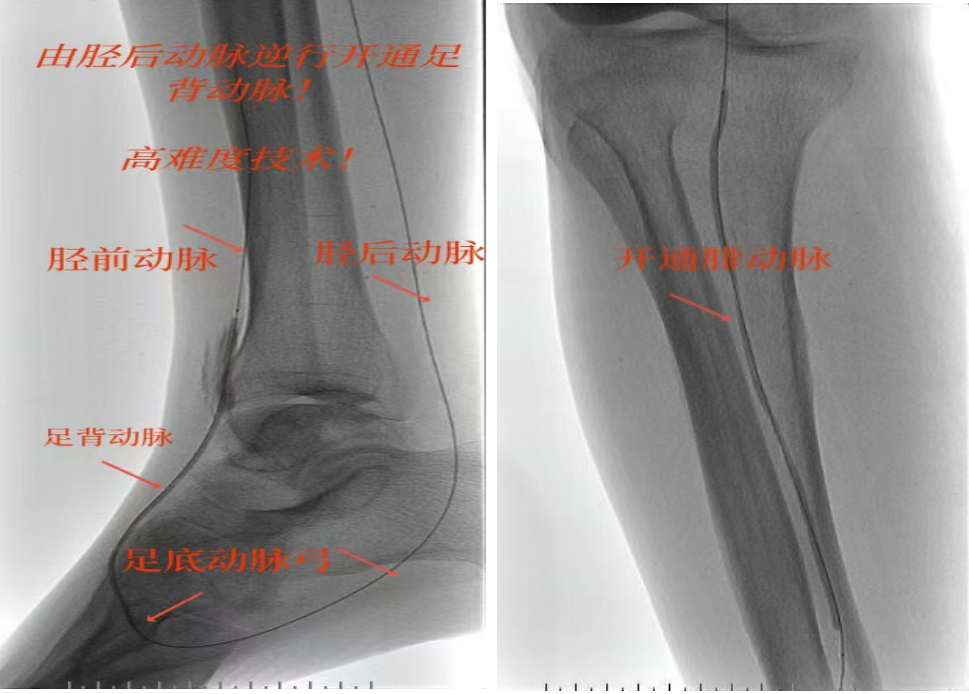

绝处逢生!“糖足”患者免截肢|市中医医院高难度介入“逆行破冰”立大功!